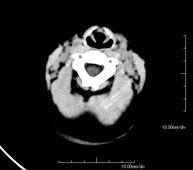

- TC Cráneo

Prueba radiológica que consiste en obtener imágenes del cráneo de alta definición anatómica (tronco cerebral, cerebelo, cerebro, calota craneal, etc.), mediante el empleo de un equipo de TC (Tomografía Computarizada).Indicaciones: traumatismos, cefalea, trastornos de la memoria, pérdida de fuerza súbita en una extremidad o mitad del cuerpo. - TC Cuello

Prueba radiológica que consiste en obtener imágenes del cráneo de alta definición anatómica mediante el empleo de un equipo de TC (Tomografía Computarizada). Indicaciones: cefalea, estudio de tumores, traumatismo craneal. - TC Cuello